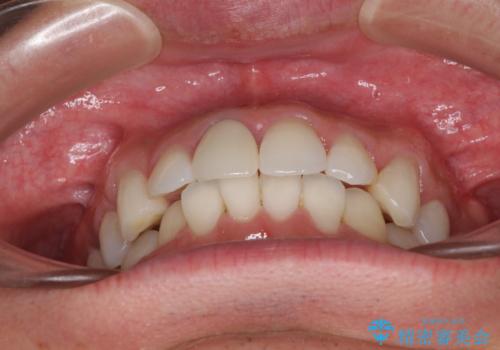

口が閉じにくい インビザラインによる矯正治療

- 口の閉じにくさを気にして来院された患者様です。

患者様と相談の上、横顔の印象から抜歯矯正は必要ないと判断し、IPR(歯と歯の間)並びに歯列全体の後方移動により口元の突出感の改善することとしました。

しっかりと装着時間を守り、ゴムかけも徹底していただいたので、思いの外口元を引っ込めることができました。

これ以上の改善を望まれましたが、非抜歯矯正でこれ以上口元を引っ込めると食いしばりすやすい咬合となるため、この歯列で終了としました。